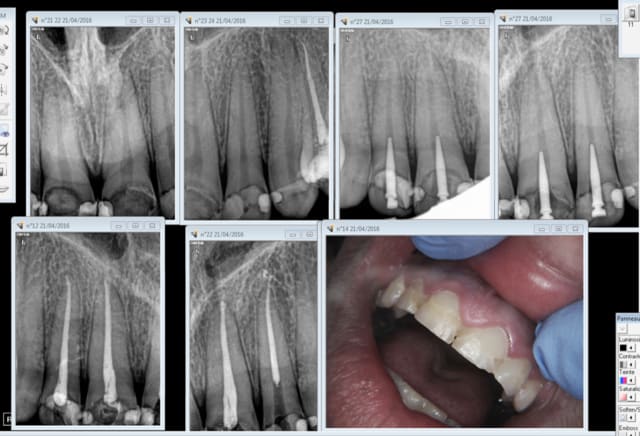

21/04/2016 à 14h14

Yes ! -)

Capture d e cran 2016 04 21 12.12 - Eugenol

chicot29

21/04/2016 à 18h58

Ben tiens, de mieux en mieux On ne change pas une équipe qui gagne. Enfin bon ca a ses limites motif de la consult à votre avis ? -)

Capture d e cran 2016 04 21 16.54 - Eugenol